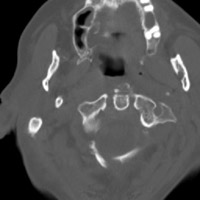

- Click on the image for a larger versionDAxial CT. This image depicts the severe fracture of the anterior arch of C1.